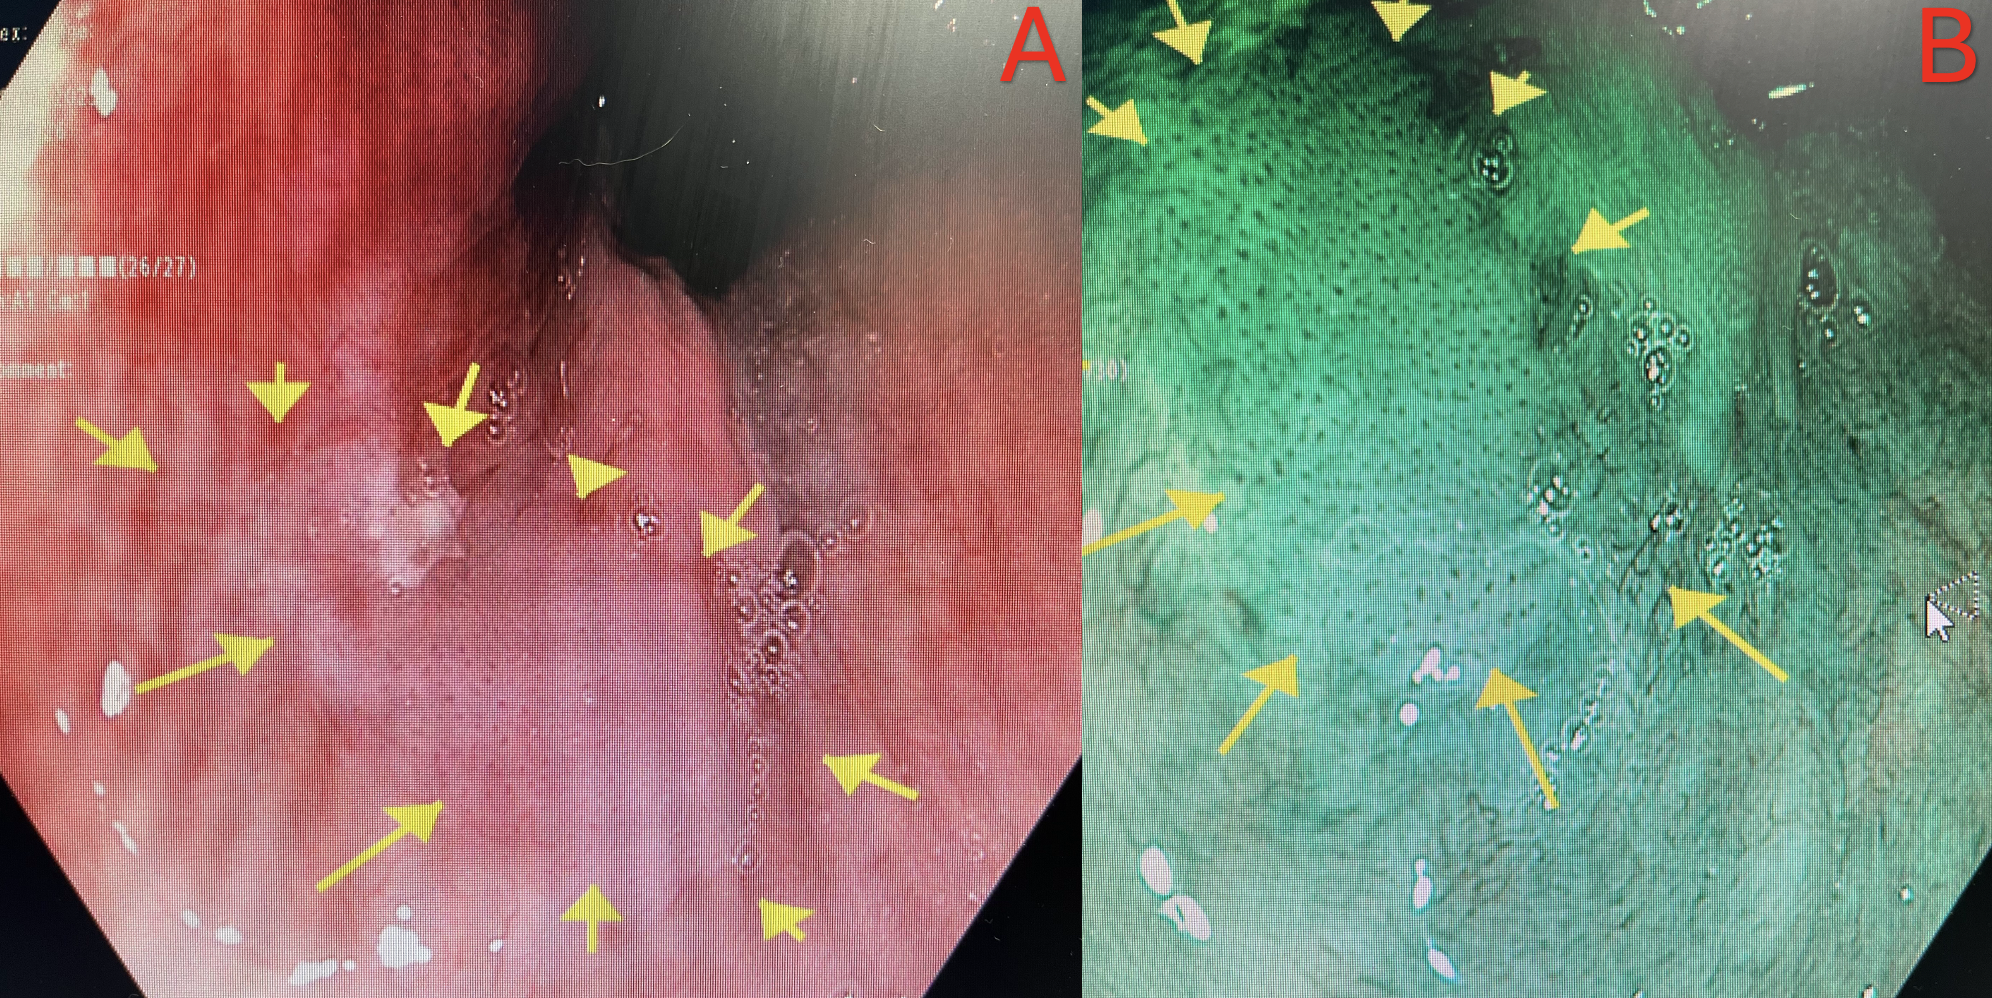

A, slightly raised areas of thickened distal rectal mucosa. B, irregular blood vessel mosaic appearance of the mucosa during retroflexion using narrow-band imaging, Pathology revealed it as AIN III in immunocompetent patient.